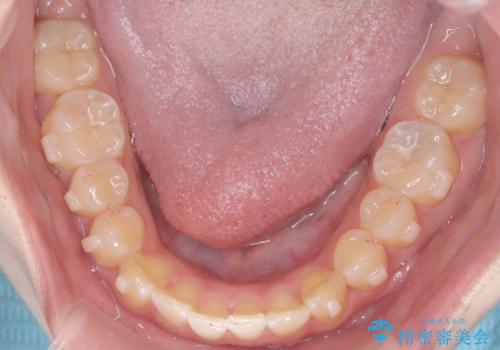

【インビザライン】オープンバイト。凸凹を治したい

- オープンバイトを主訴に来院されました。

インビザラインを用いIPRと遠心移動を行いオープンバイトと叢生の改善を行なっております。

前歯の叢生がわずかにありますが、追加アライナーの作成は希望されなかったため、歯を動かしていく動的治療は終了となりました。